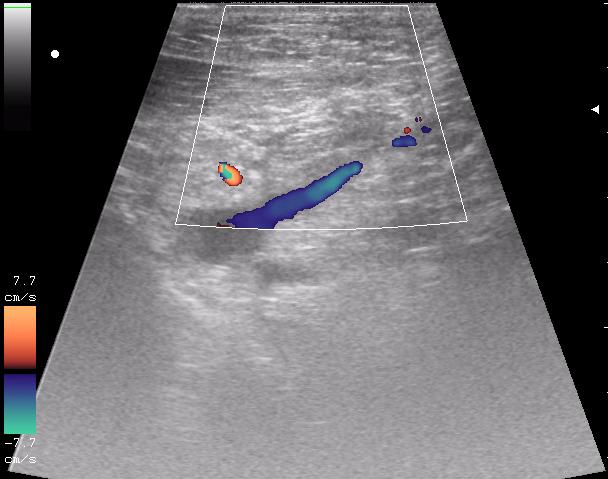

перелом ключицы, большой отек, травматолог хотел определится с тактикой...

и в отношении второго снимка: там какой именно сосудистый пучок? - и что именно исключали этим сканом

исключали повреждение отломками подключичную артерию и вену ( был огроменный отек)

кстати, вот вена